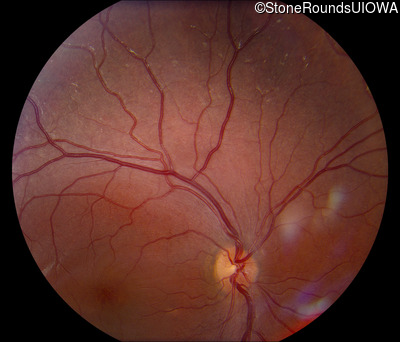

Fundus Photography - Right - 20/32 -1

Exemplar